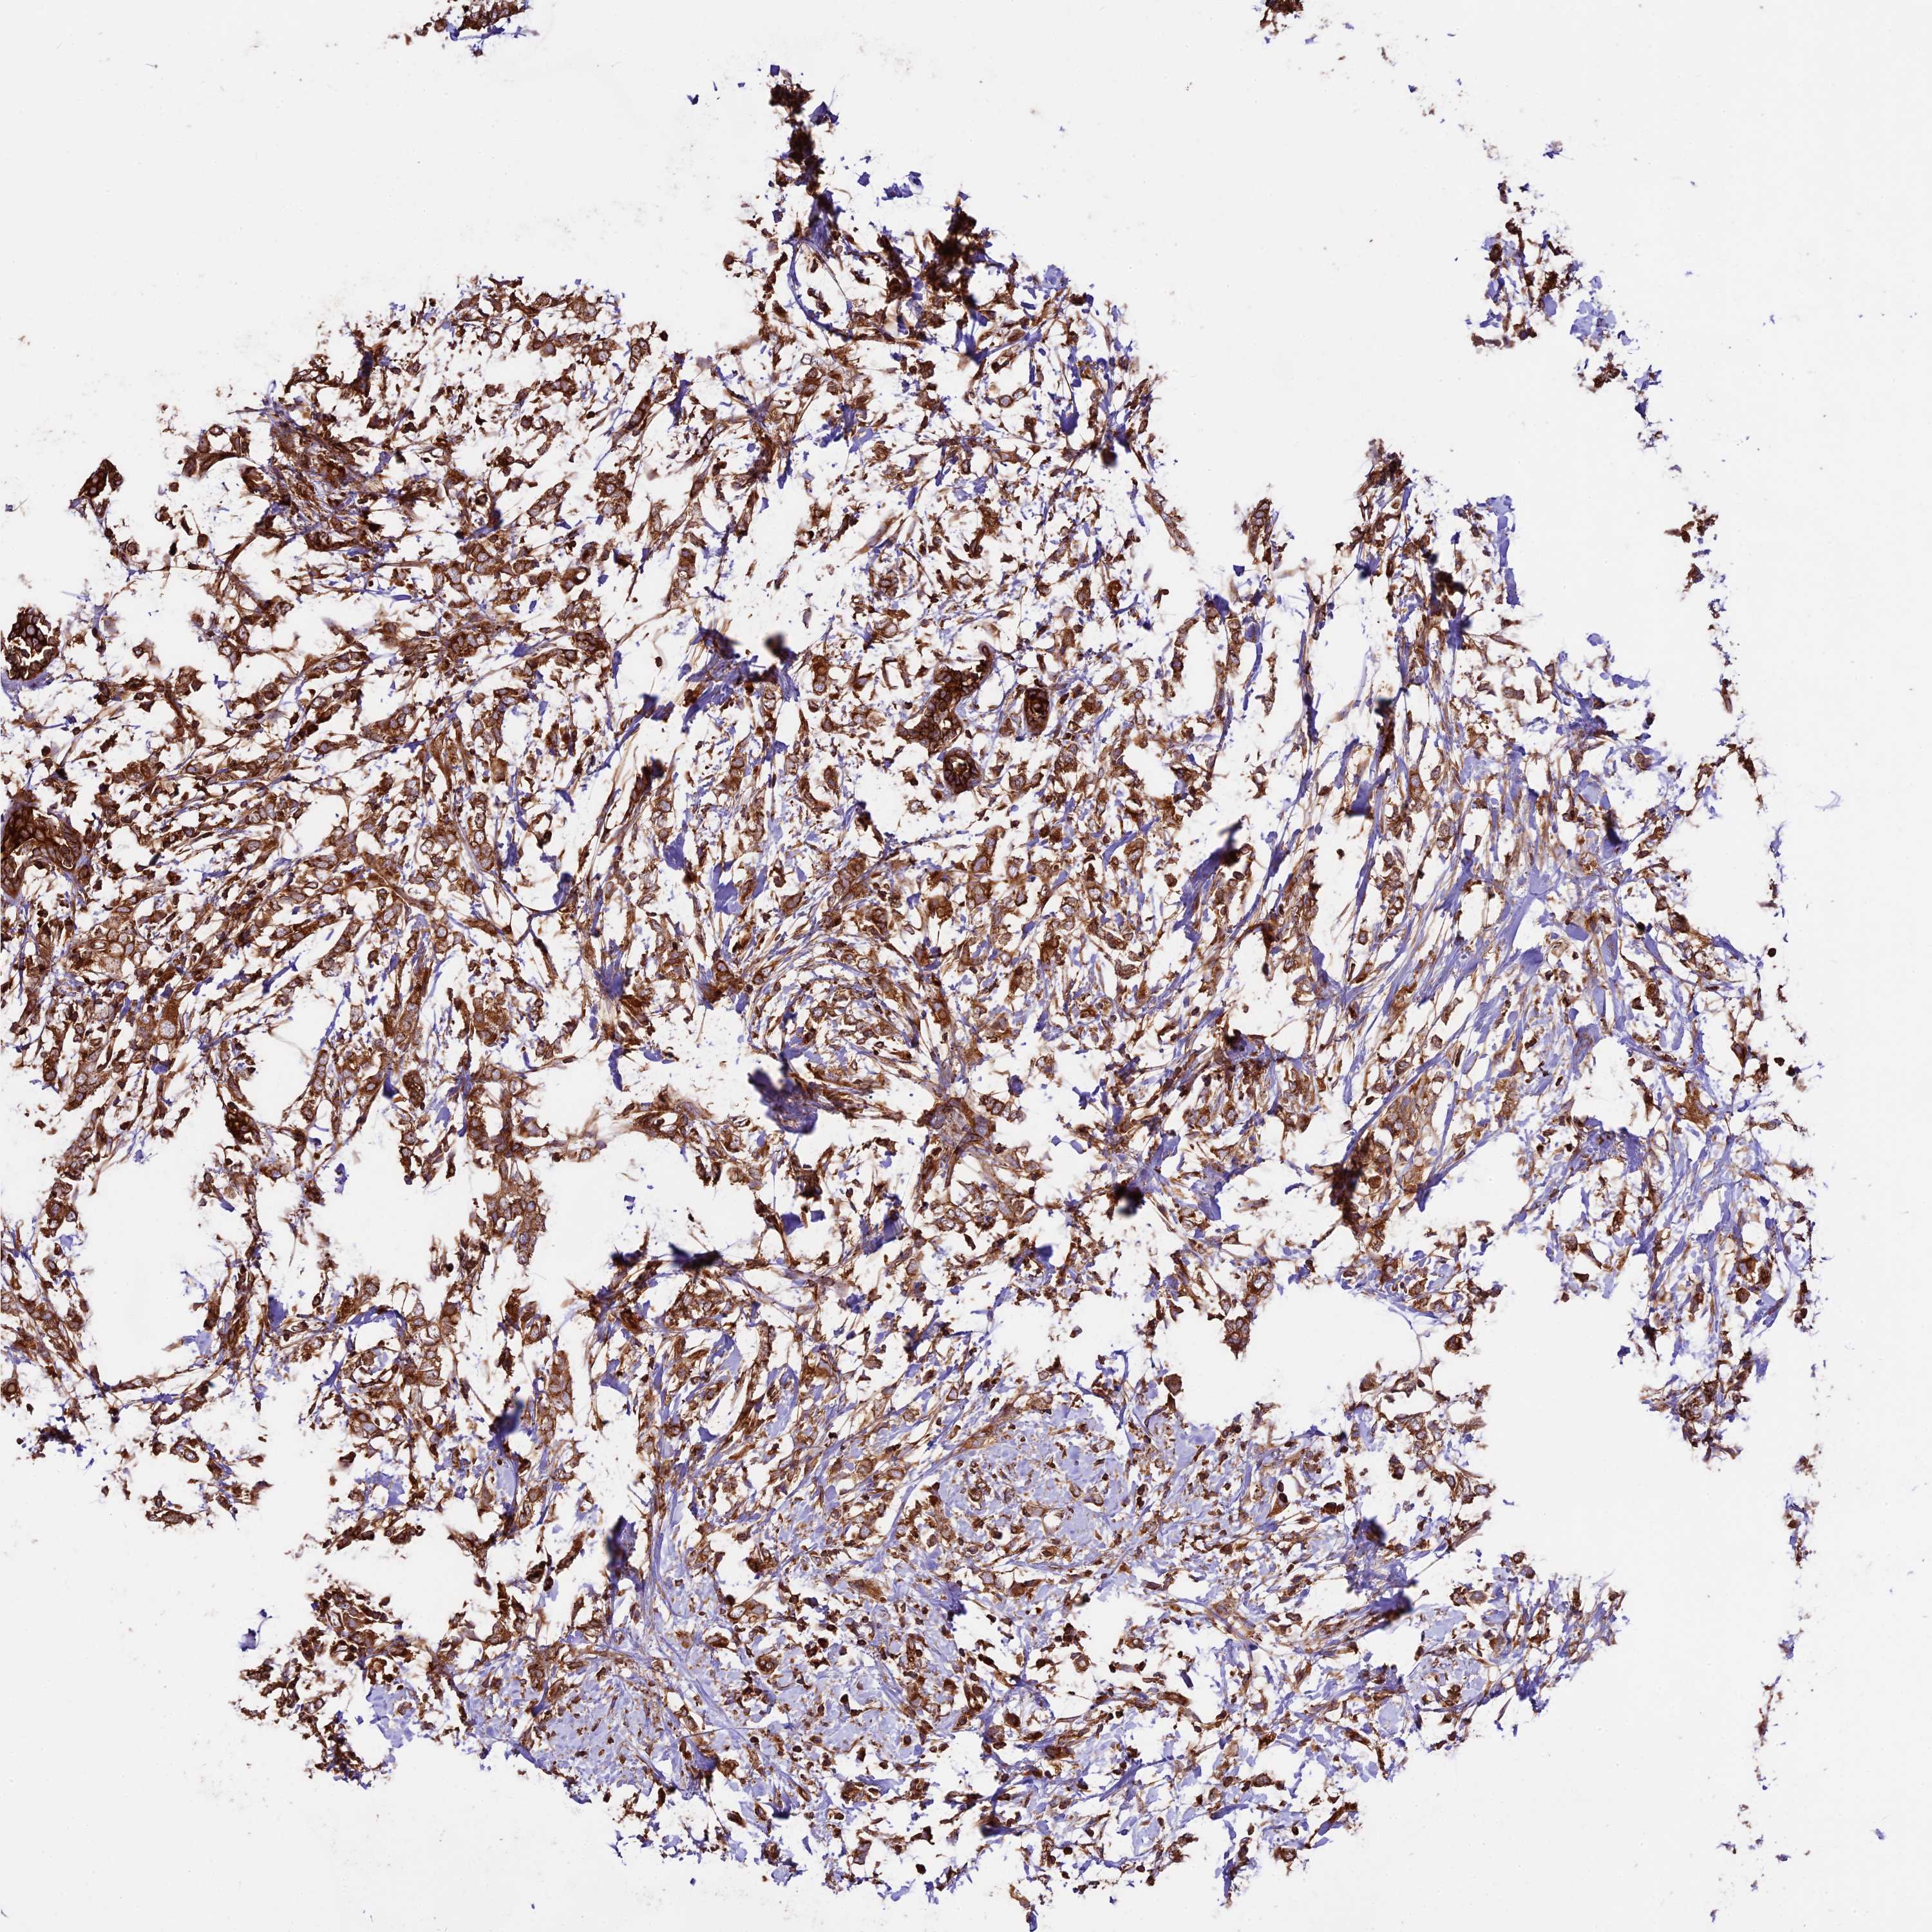

CANCER BREAST CANCER Show tissue menu

BRCA TCGA BRCA VALIDATION PROTEIN EXPRESSION